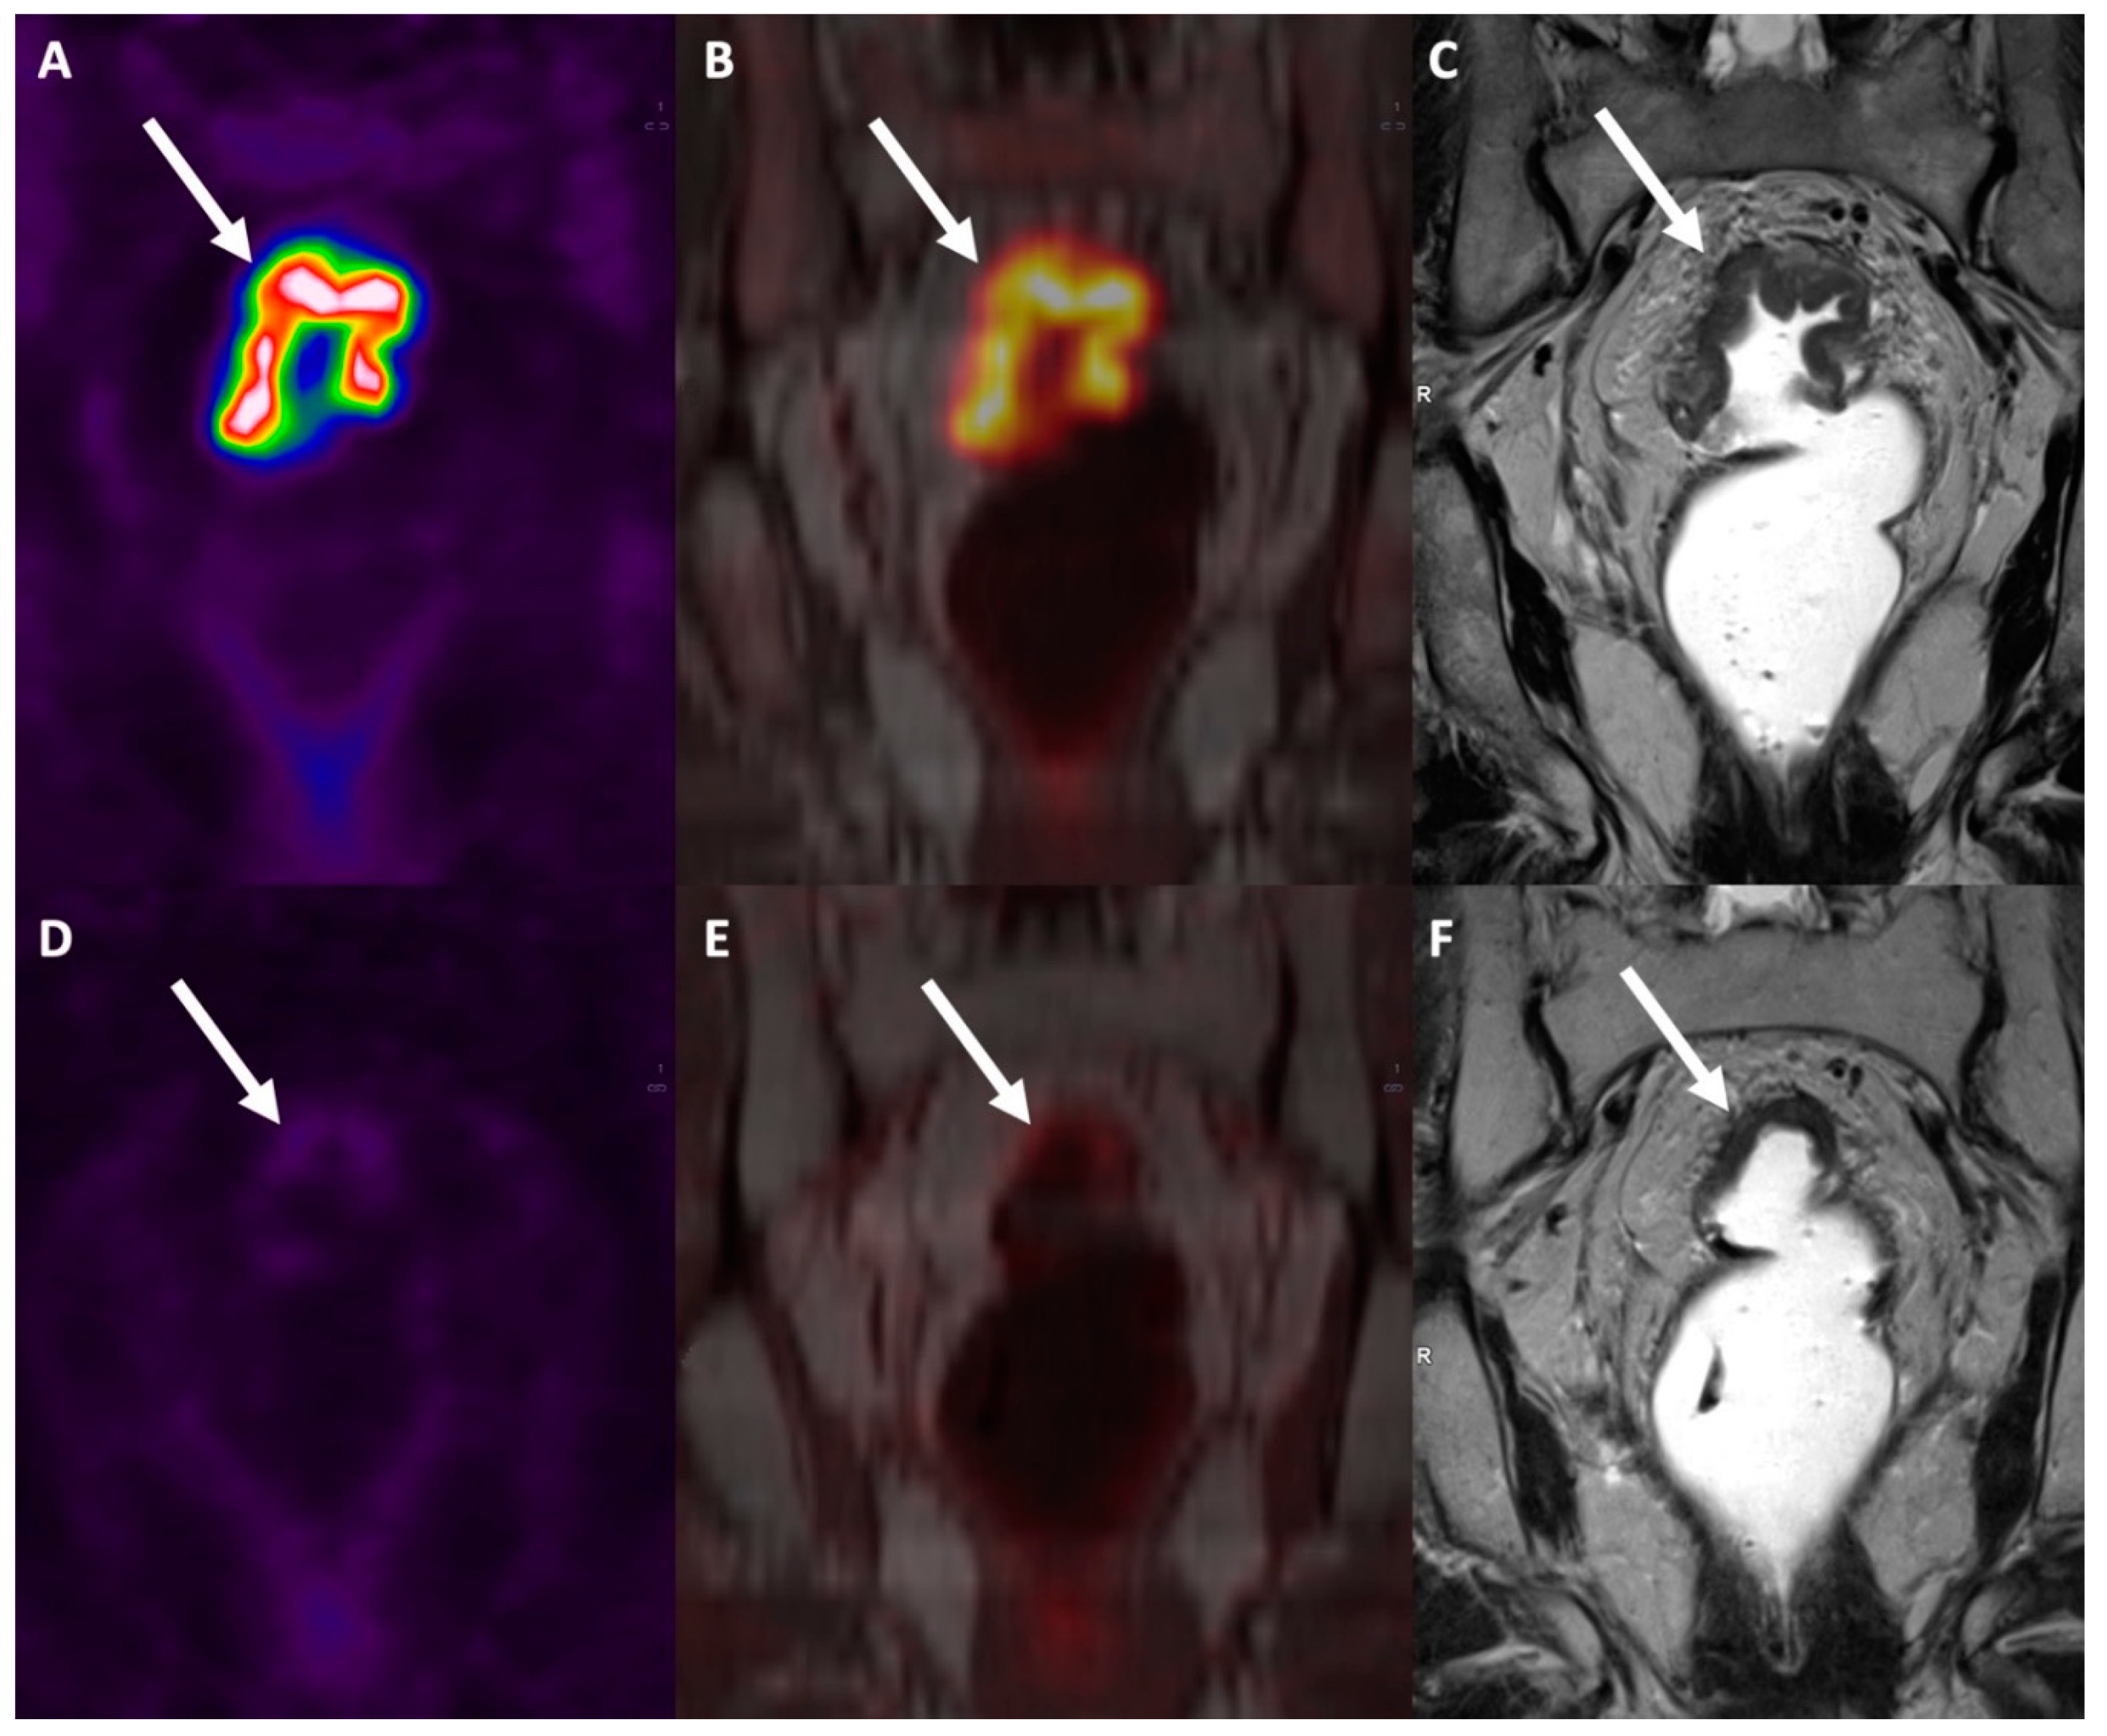

Combined [18F]FDG PET/MRI has recently been proposed as an effective imaging modality for rectal cancer patients, capable of generating high-resolution anatomical and functional data. This combined imaging modality can also spare patients the radiation exposure associated with the CT component of PET/CT. PET/MRI achieves a high soft-tissue contrast that is useful for delineating local tumor extent, and it can be implemented with ‘functional’ MR sequences like diffusion-weighted imaging (DWI) (Jayaprakasam et al., 2023) .

In a recent meta-analysis, the sensitivity and specificity for T staging, N staging and M staging in colorectal patients was 95%/79%, 81%/88% and 97%/93%, respectively (Mirshahvalad et al., 2022). While focusing on rectal cancer, PET/MRI thanks to its good accuracy in T and N staging showed to be a good tool for restaging after nCRT [Figure 8] and to address patients toward rectum-sparing techniques, while for M staging there is an intrinsic weakness for the lung parenchyma evaluation (Crimì et al., 2021).